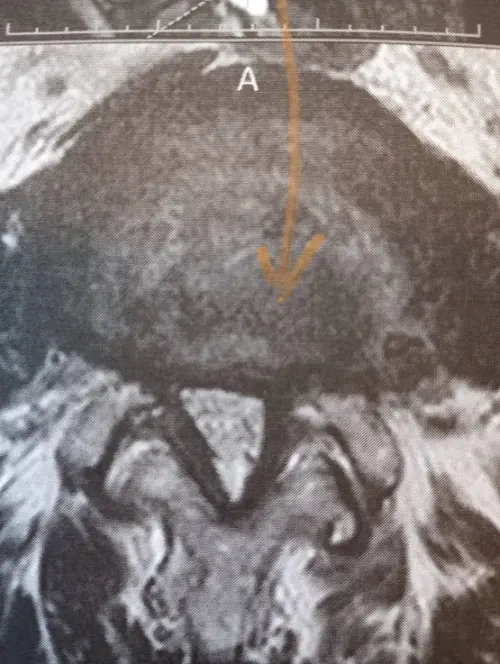

ひとことで「腰痛」といっても、その原因はさまざまです。この年代に多いのが、脊柱管狭窄症や腰椎ヘルニアによるもの。どちらも背骨まわりの構造が変化することで、神経が圧迫されて痛みや足の痺れが出やすくなります。特に脊柱管狭窄症は「少し歩くと足が重くなって、休むとまた歩ける」という特徴的な症状が出ることがあります。

背骨は積み木のように骨が重なって作られています。年齢とともに骨と骨の間のクッション(椎間板)が薄くなったり、背骨を支える筋肉が弱くなったりすることで、神経の通り道が狭くなることがあります。それが腰痛や足の痺れにつながっていくことがあるのです。また、長年の姿勢のクセや仕事中の体の使い方も、じわじわと腰への負担を積み重ねていきます。

脊柱管狭窄症や腰椎ヘルニアが疑われる状態では、まず整形外科での診断を受けることが大切です。その上で、保存療法(手術をしない治療)の一環として鍼灸や整体を取り入れる方も増えています。詳しくは脊柱管狭窄症の施術についてこちらのページもご覧ください。